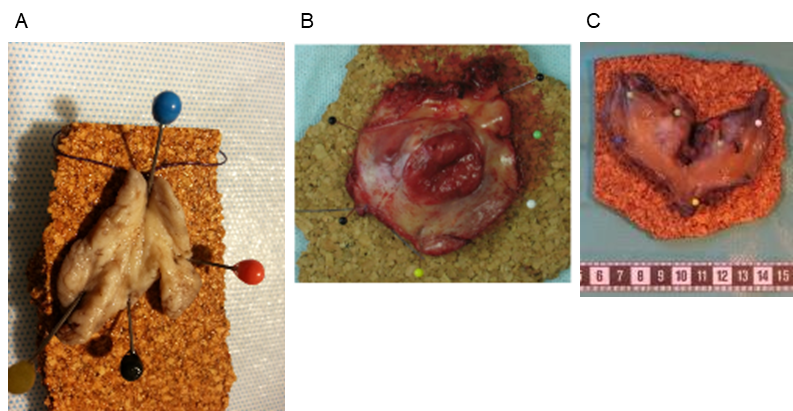

Figur 1:

Mindre excisionspreparat uppnålat på korkplatta (A), medelstort excisionspreparat uppnålat på korkplatta (B) och posterior partiell vulvektomi (C). Om vissa anatomiska strukturer eller resektionsränder är av intresse, kan dessa med fördel markeras med särskild färg på nålen eller med tusch.